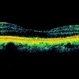

- choroidal neovascular membrane (CNVM)

- Jason Griffith, Tennessee Retina, Nashville, TN

- Photograph of a 45 year old male with CNVM.